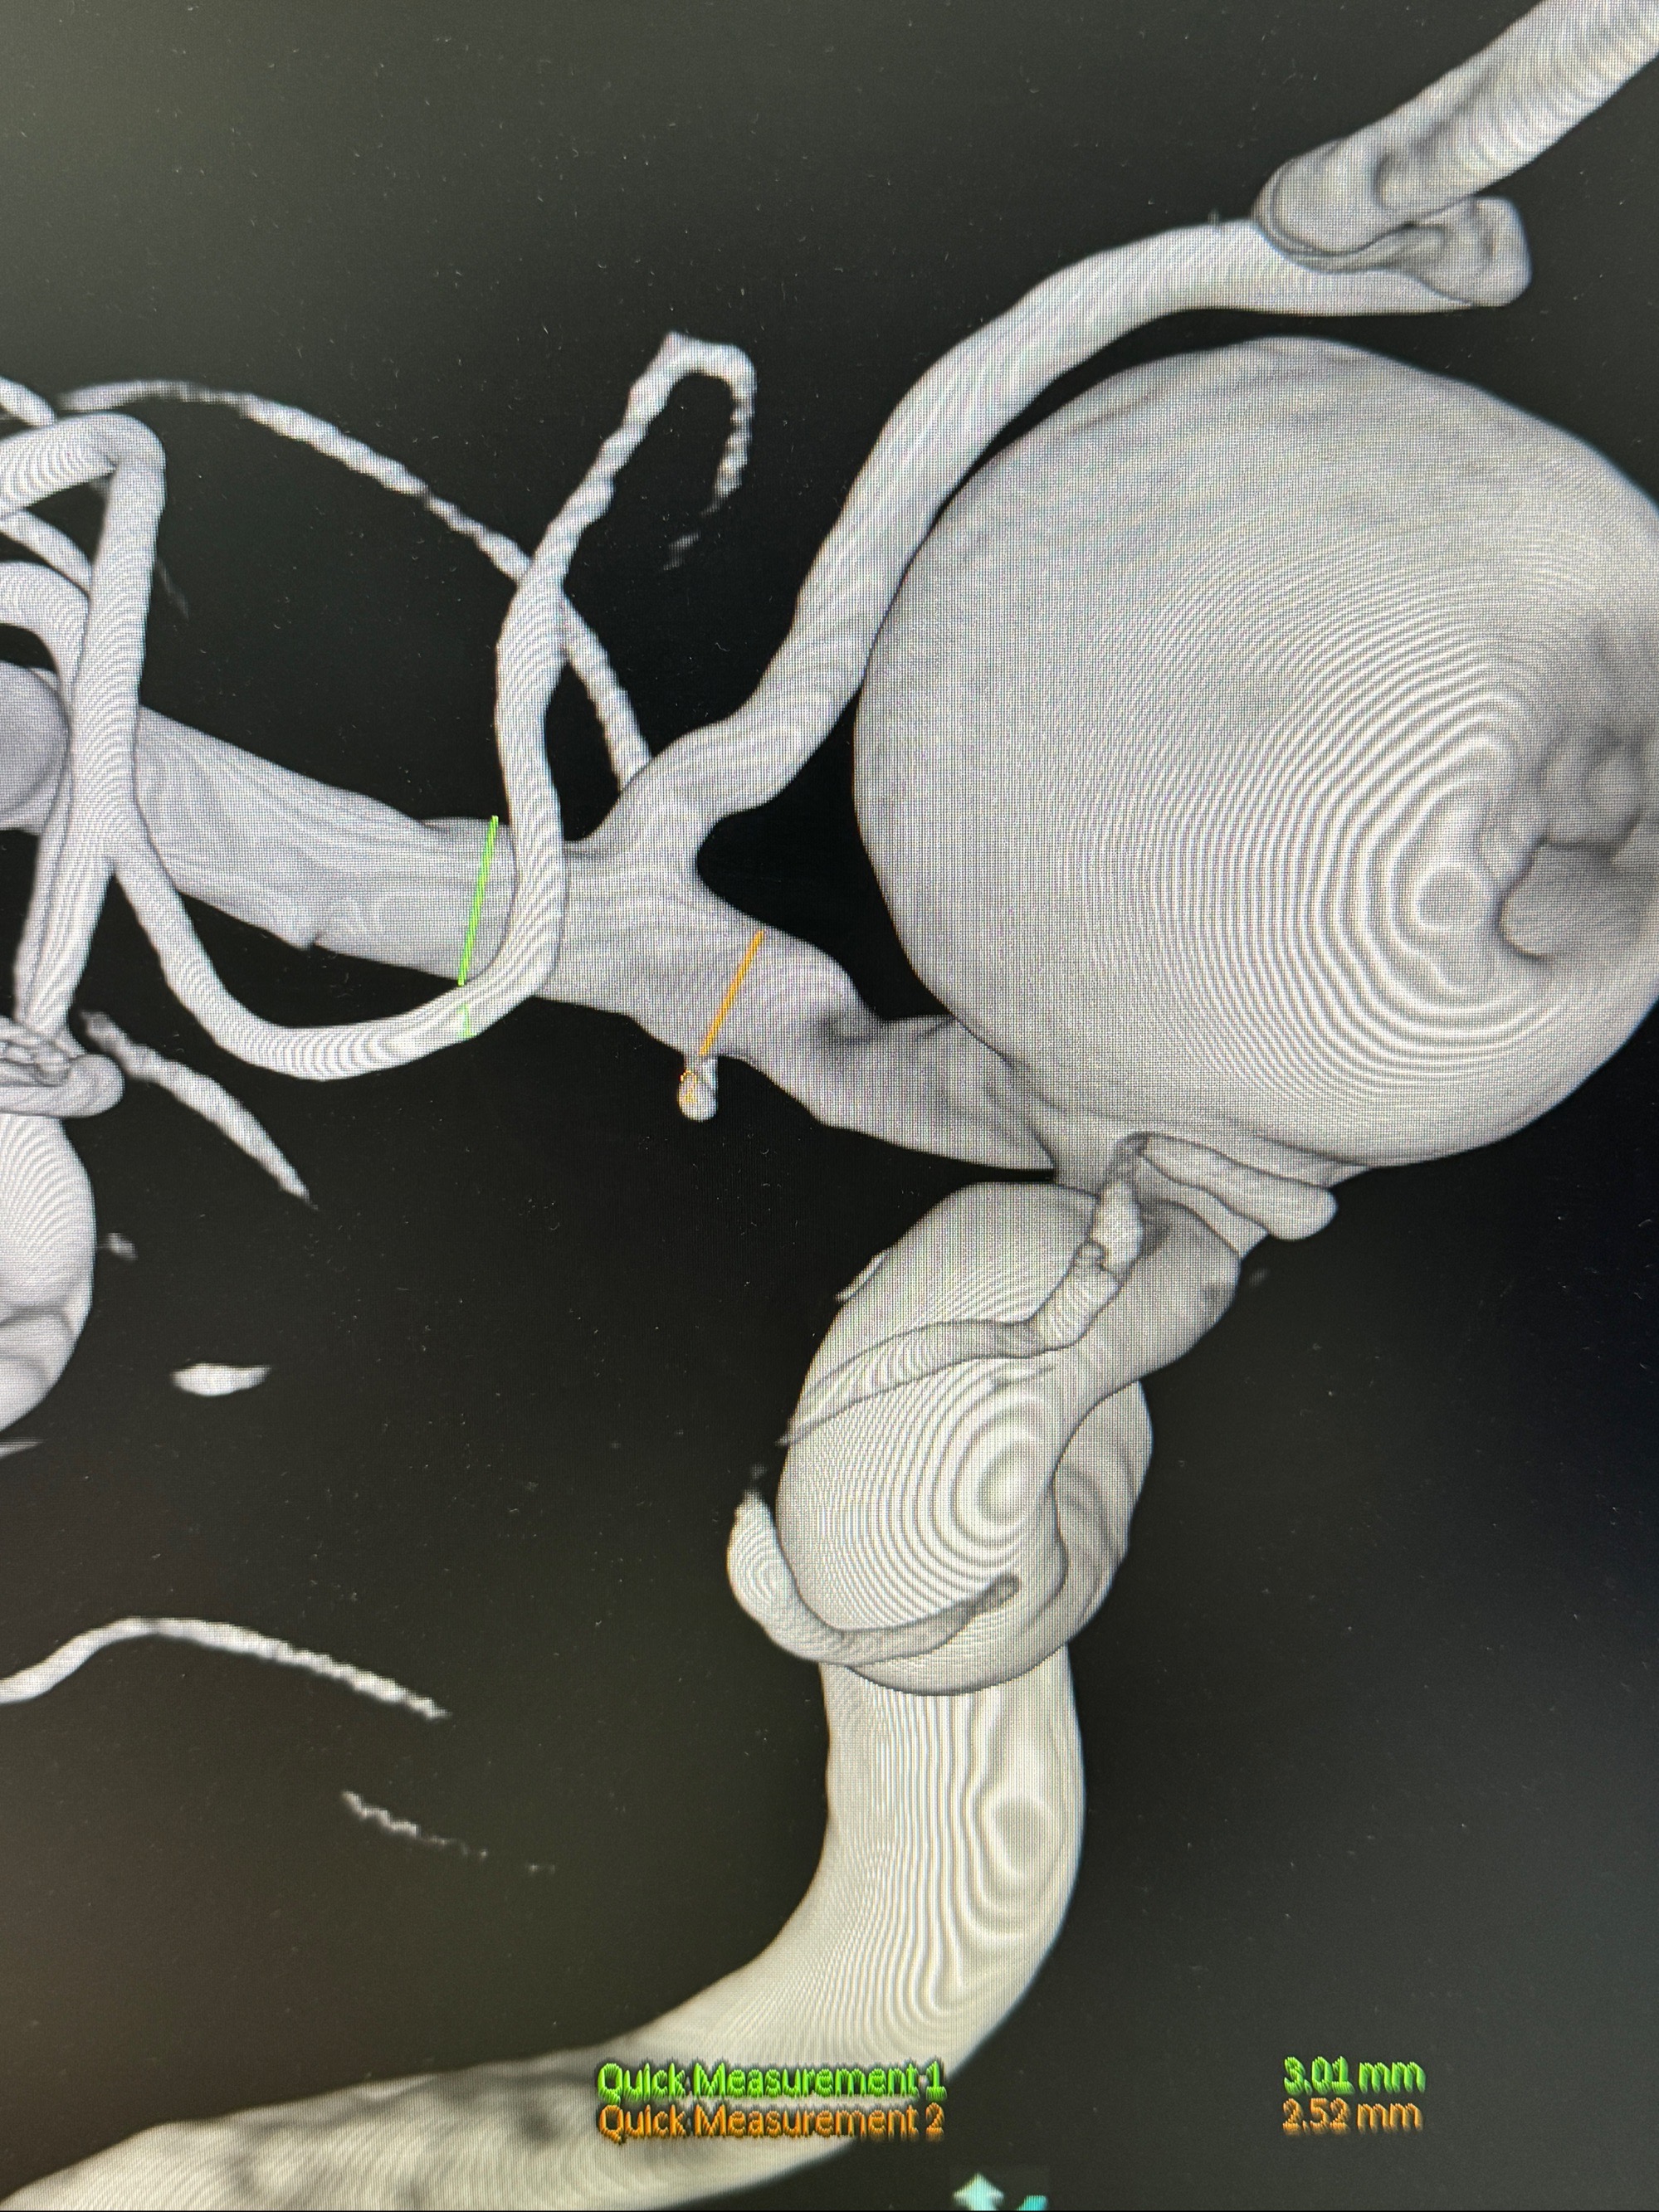

旋转3D展示动脉瘤局部的血管构筑

测量动脉瘤的大小:16*13.8*7.6mm大小,较原先变大,考虑双抗后瘤内血栓溶解可能

观察动脉瘤腔内的血流动力学情况